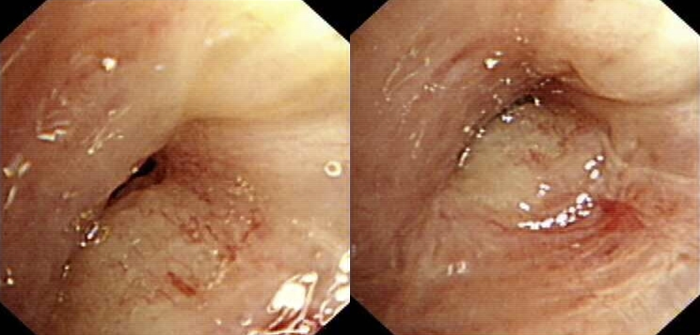

2020-11-12支气管镜检查:中叶管口充血肿胀,有肿块突出管腔致管口阻塞90%,表面不光滑,给予灌洗、针吸活检、常规活检及刷检。右下基底段气管结构扭曲变形,粘膜粗隆,未见新生物。

图2.支气管镜检查

2020-11-14病理结果:(支气管粘膜)结合免疫组化,符合小细胞癌。

免疫组化:CD56(+)、P40(-)、TTF-1(-)、Syn(部分+)、Ki-67(80%+)。